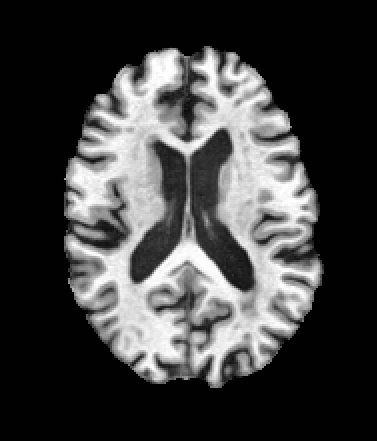

A trained MetaVoxel model can be unconditionally sampled by drawing Gaussian or categorical noise for each variable at timestep , and iteratively apply the denoising network until reaching . Unlike conventional diffusion models that focus solely on image generation, MetaVoxel can generate coherent synthetic patient profiles from the joint distribution , as shown in Figure 2.

| Age: 64.0 | Age: 53.8 | Age: 70.9 | Age: 76.9 |

| Sex: Male | Sex: Female | Sex: Female | Sex: Male |

![]() |

| Age: 80.9 | Age: 77.7 | Age: 73.2 | Age: 84.6 |

| Sex: Male | Sex: Female | Sex: Female | Sex: Female |